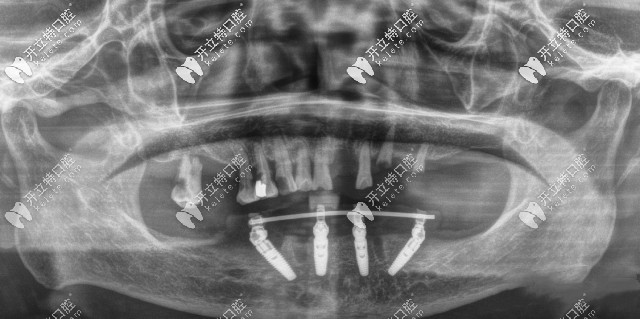

廣州廣大口腔ALLON4半口種植牙CT片

閑話不多說(shuō),大家還是來(lái)親眼見識(shí)一下廣州廣大口腔的種植牙怎么樣吧: